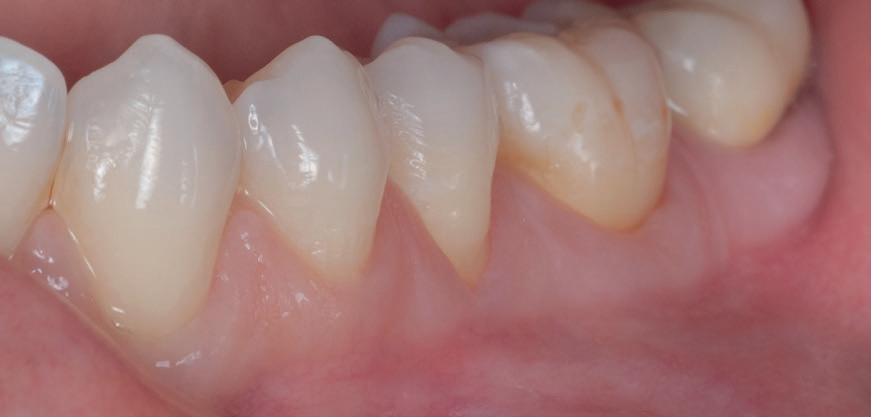

• Pacient cu restaurări deficitare pe dinți compromiși structural, tratamente endodontice eșuate, mobilitate avansată, pungi parodontale profunde, incisiv lateral absent congenital restaurat prin substituție canină inestetică, linie înaltă a zâmbetului. Rezolvarea? Colaborarea cu endodont, parodontolog, ortodont, protetician. Rezultatul? Succes clinic și satisfacția pacientului.

Caninul maxilar este un dinte de importanță capitală datorită morfologiei sale, poziției pe arcadă, funcției de protecție prin ghidajul canin și rolului în estetica zâmbetului. Poziția finală corectă a caninului pe arcadă este considerată o cheie pentru stabilitatea pe termen lung.

Un dinte impactat este unul care nu a erupt ca o consecință a unui blocaj datorat unei bariere fizice, cum ar fi un alt dinte, un chist cu dimensiuni mari, os, țesuturi moi, dinte supranumerar, odontom sau o tumoare. Al treilea molar mandibular este cel mai frecvent dinte impactat, urmat de caninii maxilari permanenți. Pentru a erupe, caninii maxilari trebuie să parcurgă o distanță mare de la marginea inferioară a orbitei până la arcadă și sunt, de asemenea, ultimii dinți anteriori care trebuie să erupă. Prevalența caninilor maxilari incluși este de aproximativ 2%, la femei de două până la trei ori mai frecvent. Două treimi dintre incluziuni sunt palatinale și doar o treime vestibulare, impactarea bilaterală având o prevalență de 8%.

Impactarea poate deplasa un dinte ca urmare a presiunii fizice, a prezenței unui chist, a resorbției radiculare (mai frecventă la incisivii laterali maxilari cu rădăcini conice orientate palatinal, dar poate fi observată și la centralii maxilari), generând durere locală sau iradiată alături de tulburări inflamatorii. Clinicienii trebuie să fie conștienți de faptul că poate exista o diferență de până la 6 luni între vârsta cronologică și cea de erupție a caninului maxilar pentru a exclude agenezia sau impactarea. Doar simpla observație a unui canin inclus fără intervenție după vârsta de 12 ani, cel mai probabil nu va rezolva situația. Diagnosticul și intervenția timpurie ajută la asigurarea unei gestionări ocluzale ulterioare mai ușoare. Dacă intervențiile timpurii eșuează, va fi necesară o soluție ortodontică chirurgicală interdisciplinară.

Pentru caninii impactați bucal și palatinal s-au recomandat protocoale ortodontice și chirurgicale, decizia bazându-se pe dovezile disponibile. În cazul caninilor cu impactare vestibulară, poziția relativă la MGJ este esențială pentru a decide care procedură chirurgicală să se utilizeze. În aceste cazuri, pot fi utilizate trei tehnici, în funcție de poziția dintelui: gingivectomie, lambou poziționat apical sau erupție închisă. La caninii cu impactare palatinală, abordarea deschisă are mai multe avantaje în raport cu tehnica erupției închise. Cu toate acestea, tehnica închisă are indicații clare.

Utilizarea mecanicii ortodontice adecvate, împreună cu respectarea principiilor biomecanice de bază reduce probabil riscul complicațiilor terapeutice. Cei trei factori esențiali constau în pregătirea unei ancorări eficiente pe arcada maxilară, utilizarea unei tehnici adezive eficiente pentru atașarea ortodontică și aplicarea vectorilor de forță corespunzători pentru tracționarea caninului pe arcadă. Posibilele complicații ale tratamentului caninilor impactați includ anchiloza dintelui, resorbția radiculară a dintelui sau a dinților adiacenți, neajunsurile estetice gingivale la nivelul caninului tratat față de caninul contralateral și duratele terapeutice prelungite.